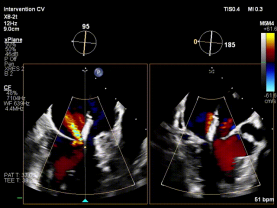

【图片6:术前超声图】

病例2为复杂功能性二尖瓣反流(FMR),术前影像提示前后瓣叶对合不良,存在明显间隙(GAP),反流程度达极重度。该类病例因瓣叶牵拉明显、张力大,是TEER技术中的典型难点。

针对该病例特点,团队制定个体化诊疗策略,在穿刺位置、器械路径及夹持方式上进行精细设计。术中,团队优化房间隔穿刺高度与位置,匹配GAP结构特点;反复调整导向系统,确保器械垂直对准反流中心;通过多平面及三维TEE确认最佳夹持窗口;采用分步夹持策略,提高瓣叶抓取成功率,确保手术过程平稳。